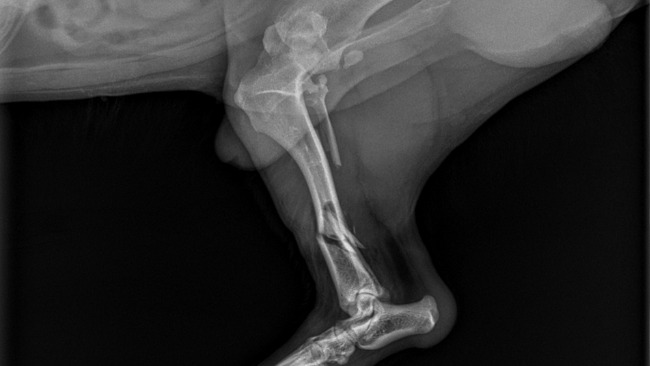

Ja, moja Żona i dwójka naszych dzieci jesteśmy właścicielami małego psa o imieniu Mike. W piątek (10-go maja) wymknął się z działki i został potrącony przez samochód, wskutek czego doznał złamania tylniej łapki w dwóch miejscach ze złamaniem otwartym. Pieniądze zostaną wykorzystane na kosztowną operację, szpital oraz leki. Pragniemy, aby nasz pies wrócił do sprawności, mógł swobodnie się poruszać, bawić się z dziećmi oraz wychodzić z nami na spacery - tak jak przed tym niefortunnym wypadkiem. Będziemy bardzo wdzięczni za każdą złotówkę wpłaconą na pomoc dla naszego Pupila. 🙏